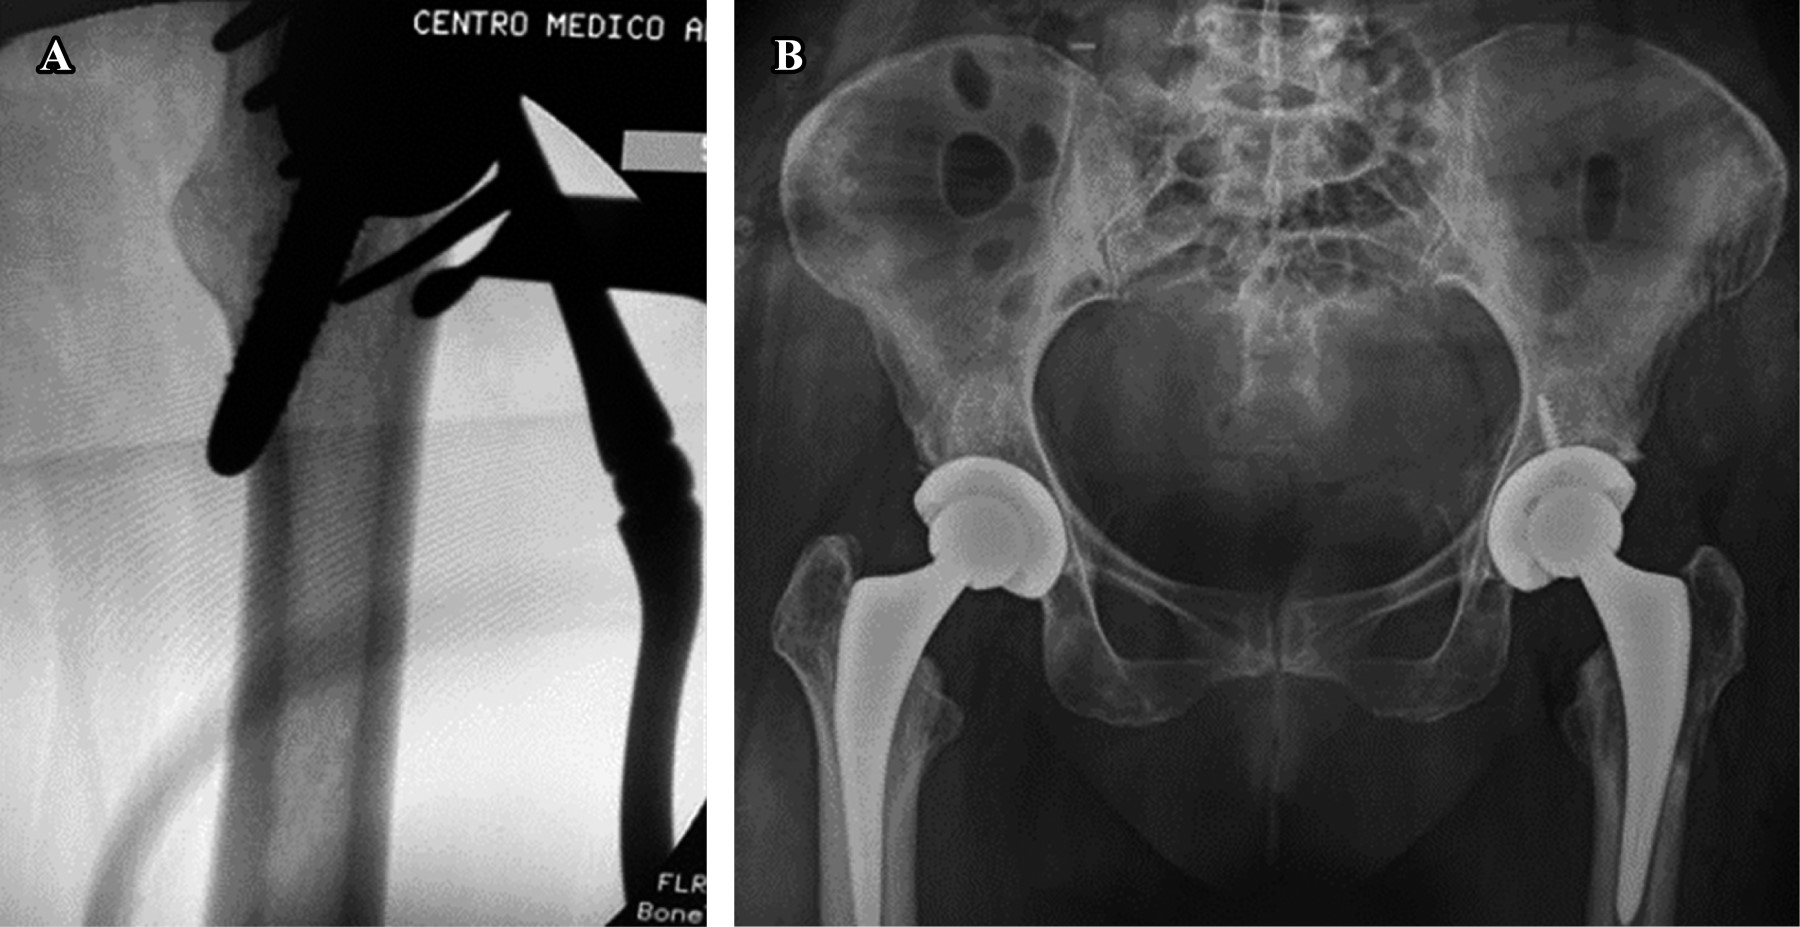

EARLY POSTOPERATIVE COMPLICATIONS

Specifically, the three main early complications are dislocation, infection, and periprosthetic fractures. Early dislocations, as with any other approach to the hip, are usually a product of component mispositioning. Unless the acetabular or femoral components have been considerably retroverted upon implantation, dislocations following the DAA are typically anterior. Due to the musculature not being detached posteriorly or anteriorly, as long as the components are well positioned, it is postulated that this approach enhances inherent stability compared with other approaches. Reported dislocation rates reported in the literature were 0.96 to 1.5%. These rates are significantly lower than the rates generally quoted for other approaches22,23 (Figure 6A-B).